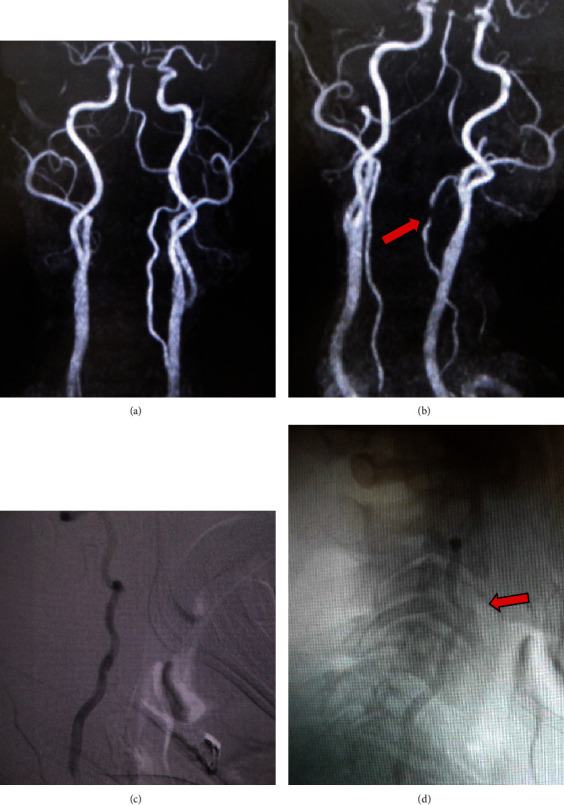

Bow hunter's syndrome is an ischemic manifestation of vertebrobasilar artery (VA) insufficiency due to stenosis or occlusion of the contralateral VA at the bony elements of the atlas and axis during neck rotation. In early reports, VA stenosis at the craniovertebral junction was the main cause, but later, symptoms due to VA occlusion at the middle and lower cervical vertebrae were also included in this pathology. Although the confirmed diagnosis is usually determined by dynamic digital subtraction angiography (DSA), we have experienced a method of minimally invasive MR angiogram (MRA) that provides the same diagnostic value as DSA and would like to present it here. The patient was a 61-year-old man who had been visiting the outpatient clinic for cervical spondylosis due to neck pain for 9 months. When he rotated his neck to the left side, dizziness and syncope appeared. Initial MRA in the neutral position did not show any steno-occlusive changes in the vertebrobasilar artery. In our hospital, repeated MRA with the neck rotated 45 degrees to the left demonstrated ipsilateral left VA severe stenosis. Subsequent DSA showed the same findings, with occlusion of the left VA. CT of the cervical spine revealed a ventral C3/4 osteophyte within the foramen. Based on these findings, instability at the C3-4 during head rotation was considered the cause of the vertebrobasilar insufficiency. The patient underwent anterior discectomy and fusion (ACDF) at the C3/4 level using a cylindrical titanium cage. Immediately after the surgery, the patient's symptoms improved dramatically and did not appear even when the neck were fully rotated to the left. More than 5 years have passed since the surgery, and the patient is still in good health.